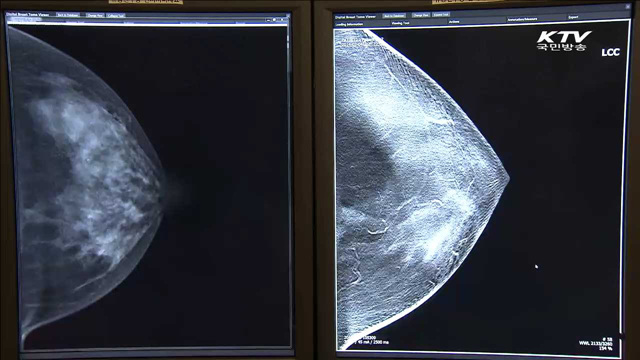

유방암 조기진단…'3차원 디지털 진단기기' 개발

여성들이 가장 많이 걸리는 암이 바로 유방암인데요, 일찍 발견하면 생존율을 크게 높일 수 있는 만큼 조기 진단이 참 중요합니다. 유방암을 쉽게 발견할 수 있는 3차원 진단기기가 국내 최초로 개발됐습니다. 김유영 기자입니다. [기사내용] 국내 최초로 개발된 3차원 디지털 유방암 진단기기입니다. 환부를 여러 방면에서 15번 촬영해 진단할 수 있는 것이...